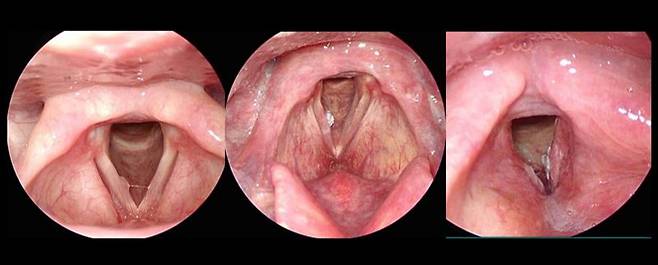

두경부암엔 후두암·구강암·인두암·침샘암 등이 있다. 성대에 발생하는 후두암은 두경부암 중 가장 많이 발생한다. 물혹, 바이러스로 인한 사마귀 조직과 달리, 단단하고 꽉 채워진 혹이 후두암의 특징이다. 후두암은 두경부암 중에서 가장 많이 발생하지만, 발생하면 바로 목소리가 변하고 전이 속도도 느린 편이기 때문에 치료 또한 가장 잘 된다. 목소리 변화가 6주 이상 지속된다면 후두암을 의심해 볼 필요가 있다.

두경부암이 의심될 경우, 먼저 내시경 검사를 통해 모양을 살펴보고 이후에 조직 검사로 확진한다. 확진되면 CT(컴퓨터단층촬영)나 MRI(자기공명영상)를 통해 범위를 확인하고 치료를 시작한다. 구강암은 수술이 일차적 치료법이며, 이 밖에도 조기에 발견된 암은 하나의 치료 방법으로 단독 치료가 가능하다.